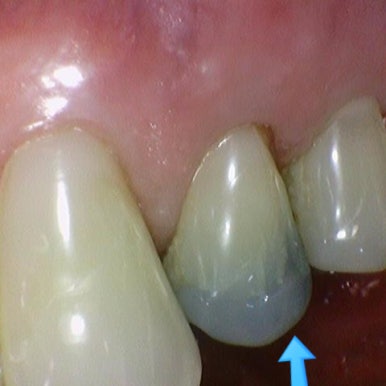

↓예전의 PFM크라운은 도자기 부분 깨진다거나

PFM은 도자기 아래 금속부분이 노출되는 등의 문제가 있었습니다.

PFM 크라운 2개를 심미 목적등으로 지르코니아크라운으로 변경. 시청역치과

위의 사진처럼 오래된 PFM크라운을 지르코니아 크라운으로 변경하기도 합니다.